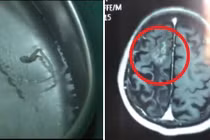

(Kiến Thức) - Người đàn ông bị cơn đau đầu hành hạ suốt 30 năm, dù có uống thuốc bao nhiêu cũng không khỏi, và chỉ mới đây, sau rất nhiều lần thăm khám, người ta mới tá hỏa phát hiện giun ký sinh trong não.

Đau đầu là một trong những căn bệnh âm ỉ, khiến chúng ta cảm thấy khó chịu nhất, vô cùng đáng sợ. Đó chính là nỗi ám ảnh của một người đàn ông ở Trung Quốc bị những cơn đau đầu như vậy hành hạ suốt 30 năm.